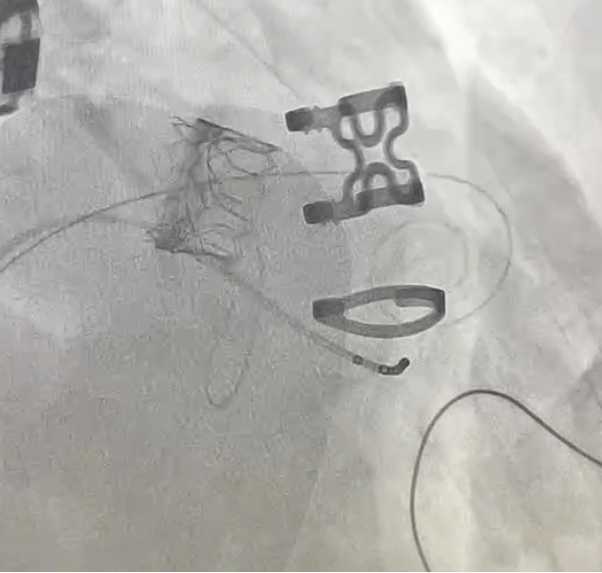

植入的新瓣膜。

3月31日,陈样新等通力合作,为龙伯成功实施了“二尖瓣瓣中瓣植入术”。由于患者原生物瓣前叶较长,为尽量减少对流出道的影响,团队采用国际先进的Lampoon(瓣叶切割)技术,在体内精准切割二尖瓣前叶,使新瓣膜植入后不易对流出道产生影响,同时大大提高了新瓣膜的贴合度。

经过近2小时的精准操作,新的瓣膜稳稳地植入衰败的瓣环上。术中心脏超声显示,二尖瓣返流几乎完全消失,瓣口面积2.3平方厘米,跨瓣压差为4毫米汞柱,瓣膜功能良好。“常规的二次开胸外科瓣膜置换手术,对龙伯这类老年患者风险极大,不仅手术复杂,还可能出现多种严重并发症。”陈样新说。